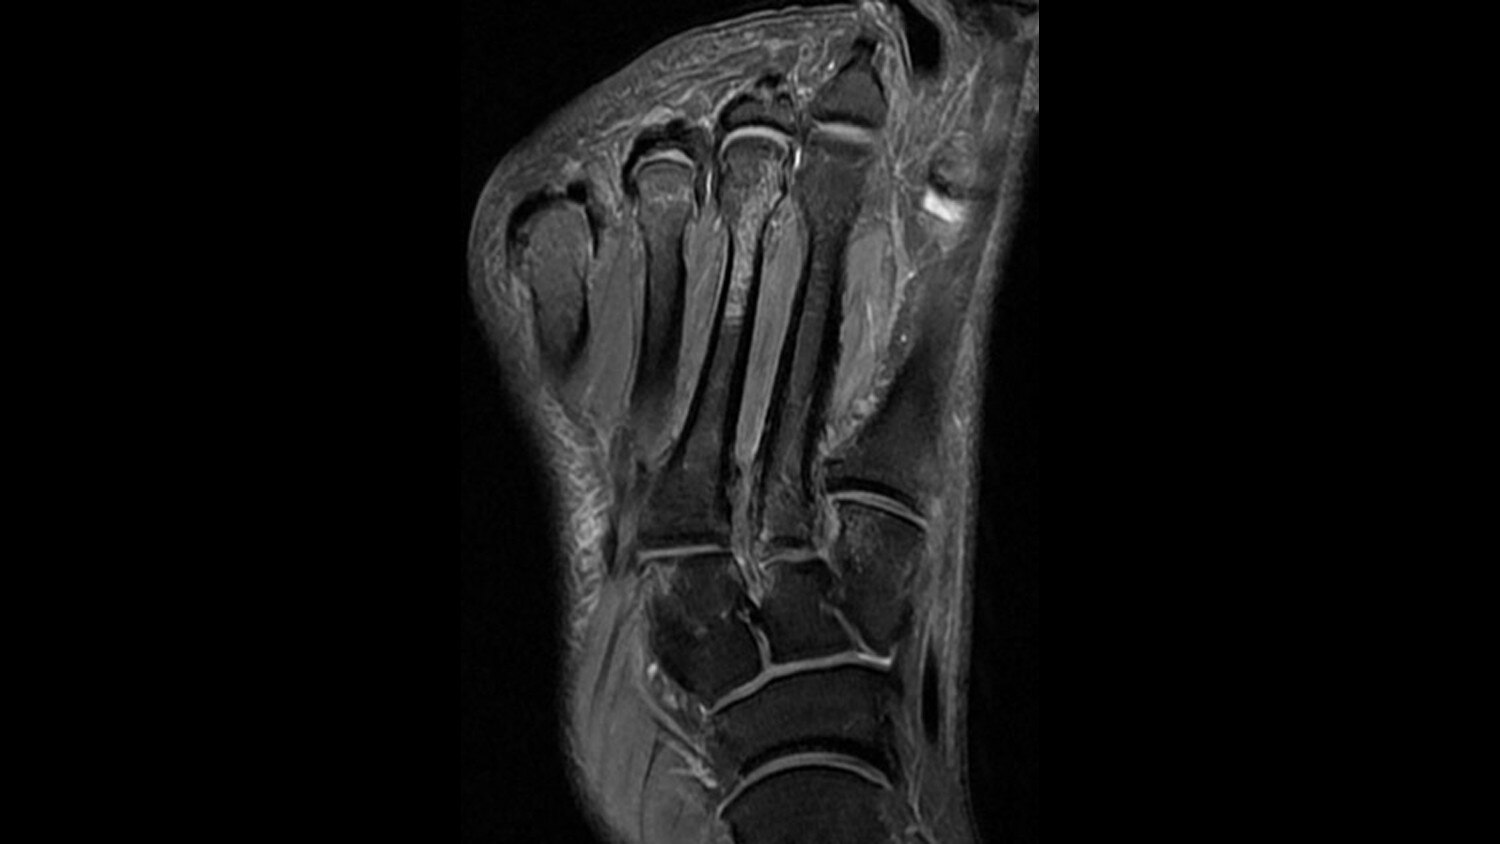

Key features include feet-first imaging for all anatomies, flexible designs that comfortably embrace the patient, comfort tilt to improve brain and neck exam form, reduced exam times through fewer coil exchanges, and comfortable variable density padding designed to help minimize pressure points. Each component of the GEM Suite can be used individually or combined for complete head-to-toe imaging.

GEM Peripheral/Vascular Array - A high-density PV / lower extremity array that facilitates imaging of the thighs and lower legs with parallel imaging in all 3 planes. The coil incorporates an innovative self-supporting hinge design between the upper and lower elements to accommodate patients of various sizes with simplified set-up.